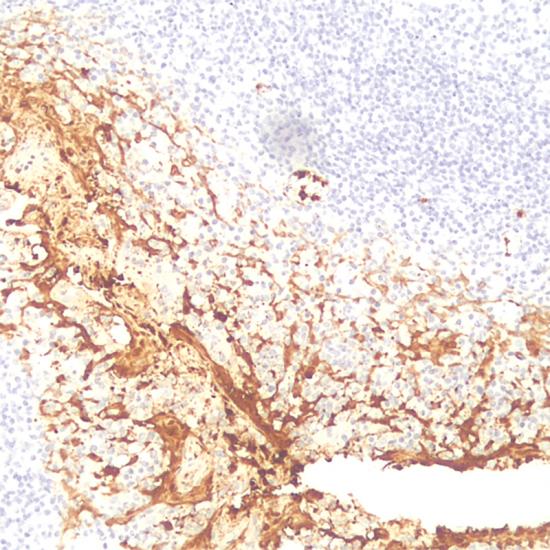

MHA主要標(biāo)記粒細(xì)胞、單核細(xì)胞和組織細(xì)胞,某些反應(yīng)性巨噬細(xì)胞,主要用于組織細(xì)胞來(lái)源腫瘤的輔助診斷,可用于標(biāo)記朗格漢斯組織細(xì)胞增生癥、真性組織細(xì)胞性淋巴瘤和某些間變性大細(xì)胞淋巴瘤等。

髓樣組織細(xì)胞抗原(Myeloid Histiocyte Antigen,MHA)抗體試劑(免疫組織化學(xué)法) 閩廈械備20190115號(hào)

細(xì)胞漿

扁桃體